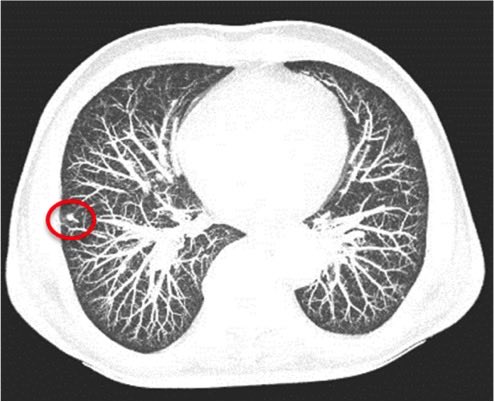

4️⃣ الكشف المبكر لسرطان الرئة: بالأشعة المقطعية قليلة الإشعاع .. ابتداءً من سن الـ٥٥، لأولئك المدخنين ما يعادل باكت يومياً لمدة ٣٠ سنة أو باكتين يومياً لمدة ١٥ سنة ..